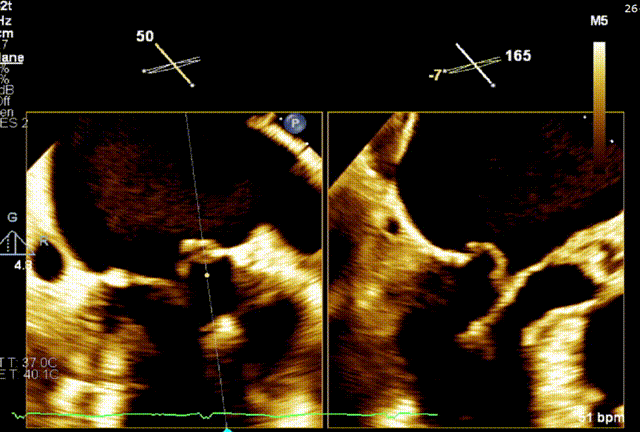

术前TEE评估

经食道超声提示,患者二尖瓣P1 commissural脱垂、腱索断裂合并重度反流(Carpentier II型/DMR4+)。

二尖瓣后瓣环明显钙化;主动脉瓣轻度钙化;三尖瓣中度功能性反流(FTR2+)。左房明显扩大;左室壁非对称性肥厚,以室间隔基底段肥厚为著(HOCM)。左室整体收缩功能正常。

二尖瓣环AP径33mm,二尖瓣后瓣环明显钙化,房间隔拟穿刺高度40mm;二尖辦脱垂宽度5.7mm,脱垂高度7.7mm,二尖瓣1区前叶长度29mm,后叶长度19mm,二尖瓣2区前叶长度23mm,后叶长度14mm,MVA=4.0cm²。

术前1区X-Plane反流情况